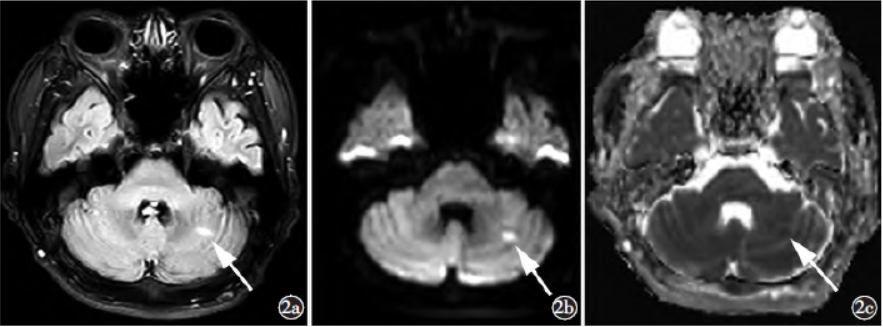

影像学检查:头颅MRI及MRA(图1~3)示双侧丘脑及左侧小脑半球多发斑片样T1WI低信号影、T2WI高信号影,T2WIFLAIR呈高信号,DWI信号随b值升高并增高,ADC呈低信号。DSA(图4)示Percheron动脉起源于左侧大脑后动脉P1段近段,右侧丘脑穿通动脉分支显影纤细,左侧丘脑穿通动脉分支血流缓慢。

图2a)T2FLAIR轴位示左侧小脑半球斑片状高信号(箭);b)DWI示左侧小脑半球病灶高信号(箭);c)ADC示左侧小脑半球病灶低信号(箭)